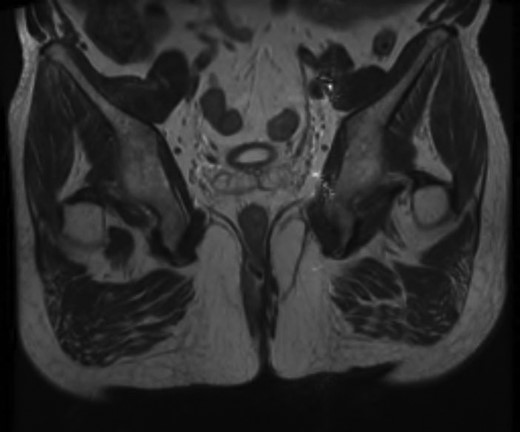

Given the high likelihood of significant vascular disease, a computed tomography (CT) angiogram was done (Fig. 1). Bilateral internal iliac artery stenosis was noted with complete occlusion of the inferior mesenteric artery and right internal iliac artery. A positron emission tomography (PET) scan showed only localized disease (Fig. 2). Magnetic resonance imaging (MRI) of his pelvis was significant for a large posterior abscess cavity with soft tissue at the margins with a cavity tracking superiorly along the posterior rectal plane (Fig. 3). The internal sphincter was noted to be necrotic on the last examination (Fig. 4) with a horseshoe cavity and a 10-cm tract running up the posterior aspect of the rectum. Multiple biopsies were taken from the anal margin, abscess cavity and peri-anal tissue, and the histology was consistent with diffuse large B-cell lymphoma. There were sheets of large atypical lymphocytes with extensive areas of necrosis. The tumour cells showed strong and diffuse immunohistochemical reactivity for CD20 (Fig. 5), indicating B-cell differentiation. The Ki67 proliferation index was very high (>90%) (Fig. 6) and there was positive in situ hybridisation (ISH) for Epstein-Barr virus (EBV) (Fig. 7). Fluorescence in situ hybridisation (FISH) was performed using a MYC dual colour break apart probe (8q24), and no rearrangement of the MYC gene region was detected. The combined morphological and FISH features were not considered to be those of Burkitt lymphoma.

Magnetic resonance image (MRI) scan showing a large posterior abscess cavity with a cavity tracking posterior to the rectum.